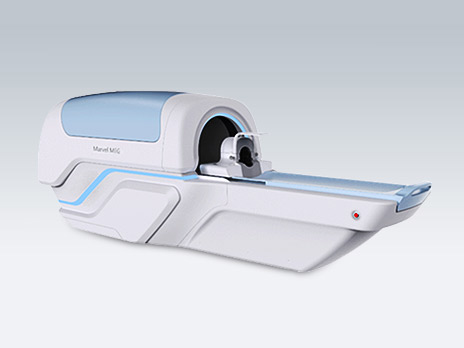

In the field of professional medical technologies and products, clinical demands are based on to target the medical technology and service market by providing solutions which range from mobile pre-hospital care to professional in-hospital surgery and covers medical devices, high-end surgical robots and medical consumables for core fields such as pre-hospital emergency, neurosurgery, orthopedics, and oncology.